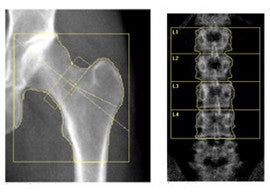

DXA is a unique imaging procedure that allows for the calculation and analysis of differential body tissues within a subject and allows for the collection of bone mineral density data. DXA imaging is performed by ARRT registered technologists trained in the rigors of clinical trial imaging and data collection.